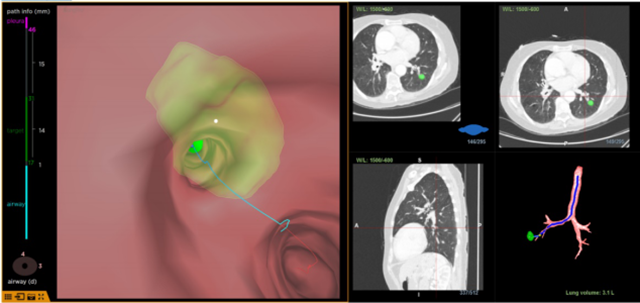

这样一位高龄且伴有多种基础疾病的患者,专家建议不宜手术。西南医科大学附属医院呼吸与危重症医学科主任李玉英立即组织专家团队进行病情讨论,并制定了精准的诊疗方案:采用气管镜导航定位肺结节,通过超声微探头确认病灶并进行活检,最后在CBCT的引导和定位下,使用“红袖刀”对肺结节进行精准消融。

李玉英介绍,大家可能对“红袖刀”比较陌生,“红袖刀”是一项近年来发展起来的气道微创介入手术新技术,它采用特制的软针经气管镜进入肺的中、外带对结节进行冷冻消融。与传统经皮消融相比,该治疗方法更具有安全性,实现了更小的损伤,效果确切且无明显毒副作用,尤其适宜于老年人群及心肺功能受限、无法接受手术治疗的患者。因其质地柔软伸展灵活,被命名为“红袖刀”。今年5月份重庆医科大学郭述良教授团队成功开展了“红袖刀”上市后国内首例手术,我院近期完成的“红袖刀”手术为四川省填补了这个空白,同时也为泸州市的肺结节患者带来了崭新的医疗服务。